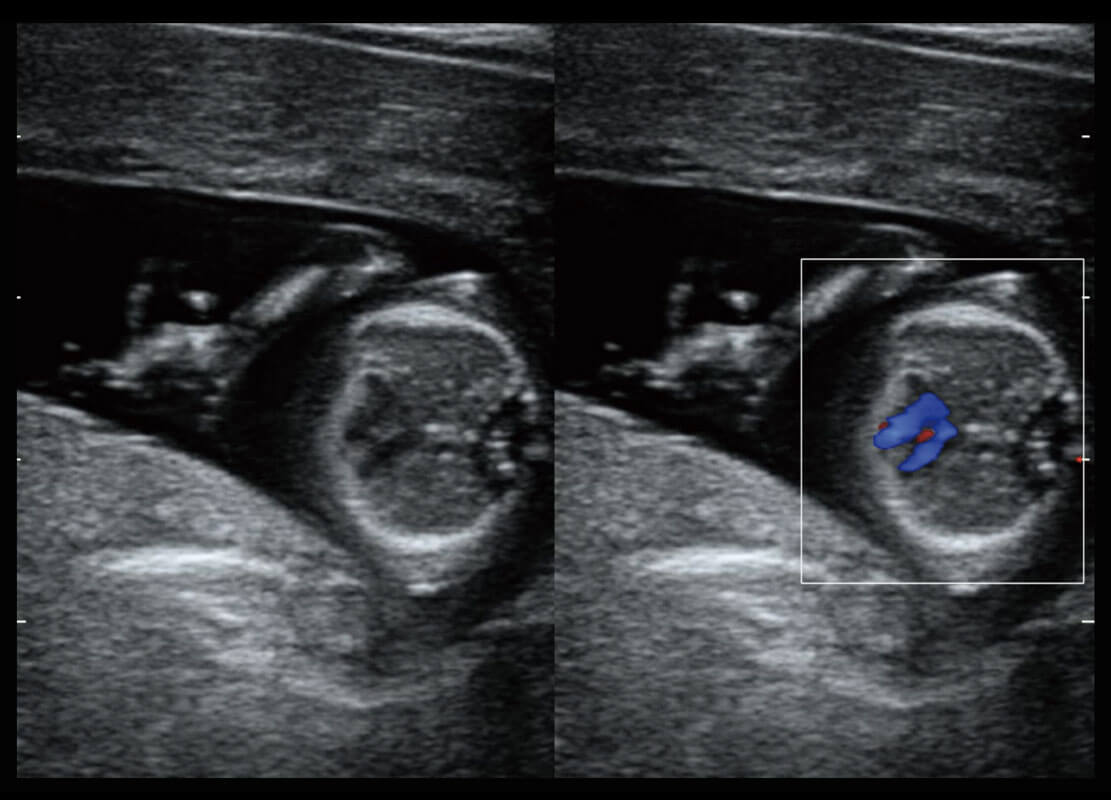

P60搭載寬頻帶線(xiàn)陣探頭、寬景成像、彈性成像技術(shù),為您提供乳腺應(yīng)用方案。P60支持高頻相控陣探頭、線(xiàn)陣探頭、腹部高頻探頭、腹部微凸探頭等,豐富的探頭群搭載敏感的彩色血流成像,適用于新生兒多種臟器檢測(cè)要求,滿(mǎn)足新生兒篩查需求。

新生兒肝血管癌

新生兒脊髓圓錐

新生兒心臟